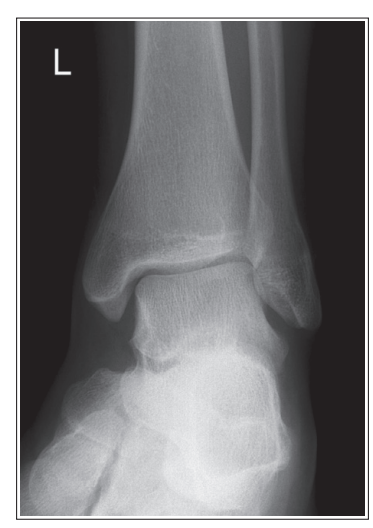

What are issues with this mortise ankle?

Insufficient obliquity/ under-rotated

the tibia superimposes more than 1/4 of the fibula, and the lateral and medial mortises are closed